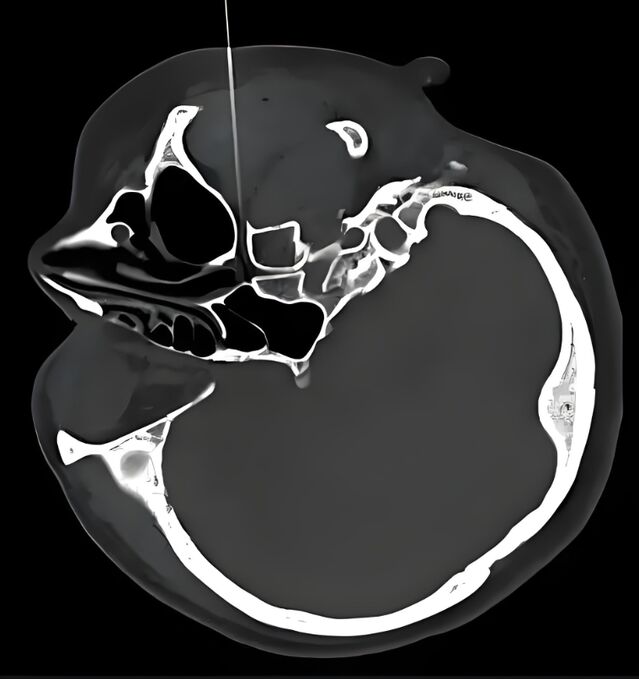

针具到位:

蝶腭神经节针刺

治疗过敏性鼻炎